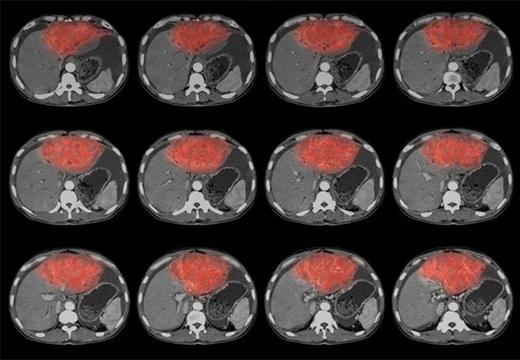

Диагностика абсцесса печени основана на инструментальных методах.?Скрининговый?вариант при?абсцессе печени – УЗ??,?которое?позволяет впервые выявить этот патологический процесс.

КТ при абсцессе печени,?проведенное?с контрастным веществом, дает более полную информацию о размерах образования, а также исключает опухолевый процесс. Проведение компьютерной томографии особенно ценно при множественных образованиях в различных отделах печени, так как метод визуализирует печень в различных плоскостях.

КТ, МРТ

Компьютерная и магнитно-резонансная томография – современные методы визуализации, часто использующиеся для диагностики поражений органов брюшной полости. Снимки позволяют выявить повреждения даже глубоких слоев ткани.

Очагово-деструктивные образования в виде гнойных полостей в печени очень хорошо видны на томограммах. Это дает возможность максимально точно диагностировать патологию и подготовиться к хирургическим манипуляциям.

МСКТ

При формировании абсцедирующей полости КТ выявляет падение плотности в центре очага до 0-2 ед. Н. При этом отмечается постепенная (кратерообразная) плотностная гетерогенность от периферии к центру. Выявляемый очаг не имеет четкого отграничения от окружающей паренхимы. Визуализируется неравномерная дольчатость, пузырьки воздуха выглядят черными точками в полости абсцесса, иногда виден уровень жидкости. При контрастировании происходит усиление капсулы без контрастирования внутреннего содержимого (при отсутствии прорыва абсцесса). По мнению некоторых авторов, диагностическая надежность КТ в случае абсцесса приближается к абсолютной.